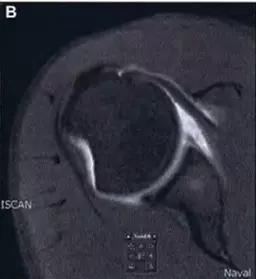

Essex-Lopresti 损伤。前后位(A)和侧位(B)示桡骨头关节内骨折(白色实线箭头);(C~E)伤后 1 个月复诊,患者诉腕关节疼痛,X 线(C,D)发现下尺桡关节脱位,(E)CT 进一步证实损伤的存在 (来源:Radiol Clin North Am. 2015 Jul;53(4):717-36)